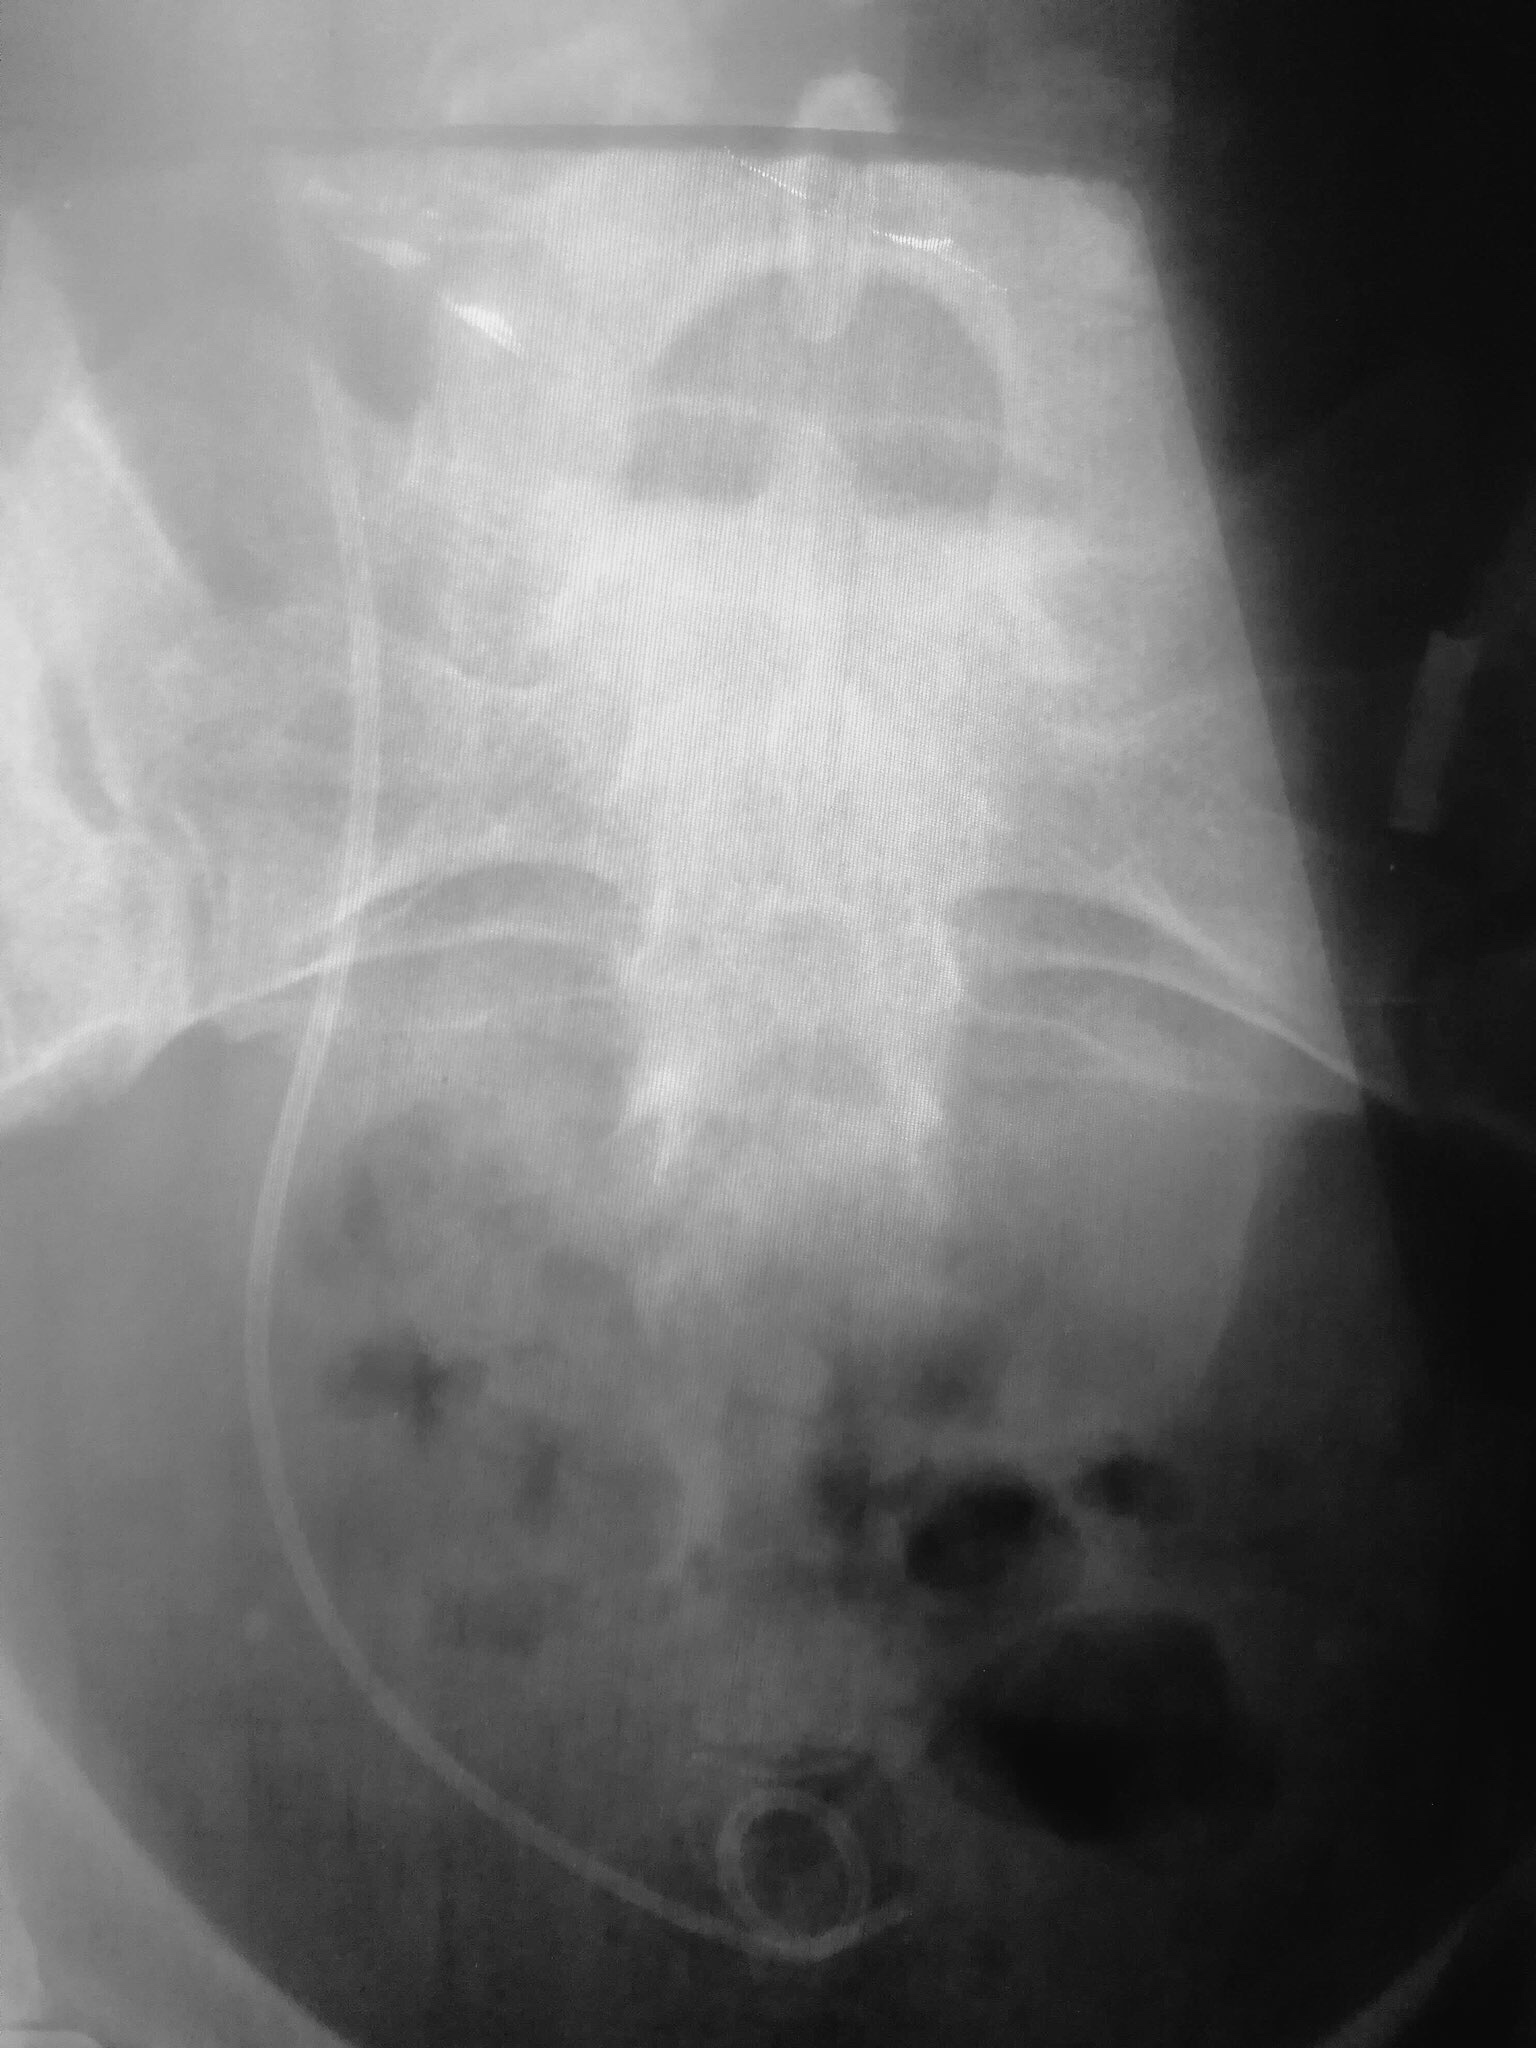

No idea what’s happening re MRI. Guess Dipstick not really interested. Why don’t MDT meetings send details to the patient? I realise patients do not go to MDTs but I hope someone somewhere advocates for the patient? so we go for MRI as instructed by text and Eric the computer spits out reminders. Then we go home and hear nothing again. Its a bit odd.